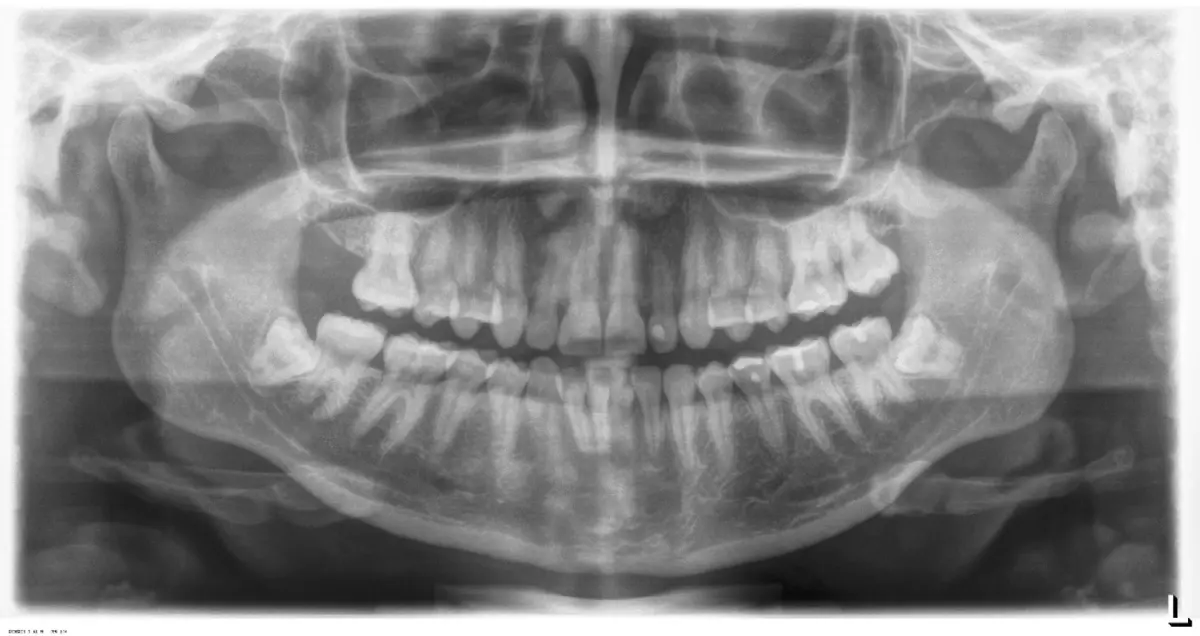

El procedimiento se inicia colocando anestesia troncular para bloqueo del nervio dentario inferior y sus ramas. Luego, se establecerá el diseño de acceso según la disposición de la molar a extraer. Para fines didácticos, se explicará cómo se realizaría la extracción de la molar de la Figura 1: se realiza una incisión horizontal a nivel de la zona retromolar hasta llegar a distal de la segunda molar, continuándose con una incisión intrasurcular hasta mesial de la segunda molar, finalizando con una incisión vertical a espesor total hasta llegar a la línea mucogingival (Figura 2).